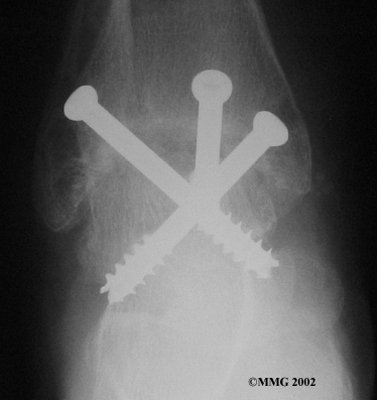

It is important when the surfaces are removed that the angles of the cut surfaces are correct. When the tibia is brought against the talus, the foot should be at a right angle to the lower leg. Once the cuts are made the bones must be held in place while they fuse. This can be done using large metal screws and metal plates if necessary. The screws are usually under the skin and are not removed unless they begin to rub and cause pain.

Inserting the screws

After ankle fusion, the physical therapists at FYZICAL Mountain Island can help you learn to walk smoothly and without a limp. Although time needed for recovery varies among patients, an ankle brace will typically replace your cast after eight to 12 weeks. Your surgeon will take X-rays frequently to see if the bones are fusing together. You will probably need to use crutches during the time you wear the cast. As the fusion grows stronger, you will begin to put more weight on your foot when walking.